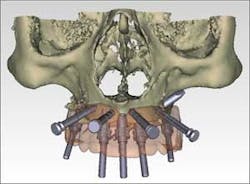

- Planning for free-hand zygoma implant placement to provide support in the maxillary posterior where there is an inadequate volume of bone for standard implants.

Following a 20-second scan, the i-CATVision scan data (in DICOM format) was imported into Nobel Biocare Procera software for further 3-D implant planning. Evaluation confirmed the inadequate volume of bone in the maxillary posterior and the need for zygomatic implants. While the thin maxillary anterior alveolar ridge would have been a significant challenge using the free-hand surgical approach, the 3-D images confirmed adequate bone volume for the precision-guided placement of anterior implants. Adequate bone volume was realized in the pterygomaxillary area where additional implants were placed for optimum posterior support. Clear 3-D orientation for the placement of zygomatic implants was reviewed prior to the procedure.

Complete dentures were fabricated in the in-house clinical lab and the mandibular immediate complete denture was converted chair side using the Teeth In A Day™ protocol. After the maxillary scanning and planning, five implants were precisely placed using NobelGuide (surgical guide), in a non-invasive flapless procedure. Two additional zygomatic implants were then placed, incorporating the knowledge of the 3-D imaging. After three months of functioning with the all-acrylic fixed implant provisional restorations, the final implant restorations were delivered. The final upper is a CM Bridge Ceramic and the lower is a CM Bridge Acrylic, (CM Ceramics, Mahwah, N.J., www.maloceramics.com/en/Mahwah.aspx), and both arches are supported by titanium framework. The patient is very excited with the esthetics and functional results of her new smile, which has restored her self-confidence. Her fixed teeth have helped her significantly in the process of becoming a certified scuba diver.